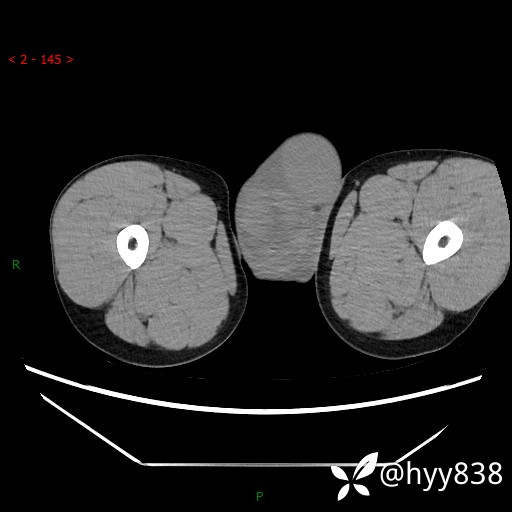

增强动脉期